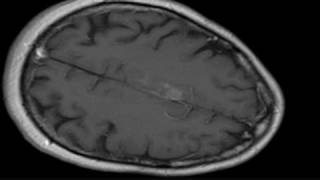

2010: New vaccine attacks brain tumor video

2010: New vaccine attacks brain tumor

2010: New vaccine attacks brain tumor Vaccine attacks brain tumors

2010: New vaccine attacks brain tumor

2010: New vaccine attacks brain tumor Vaccine attacks brain tumors